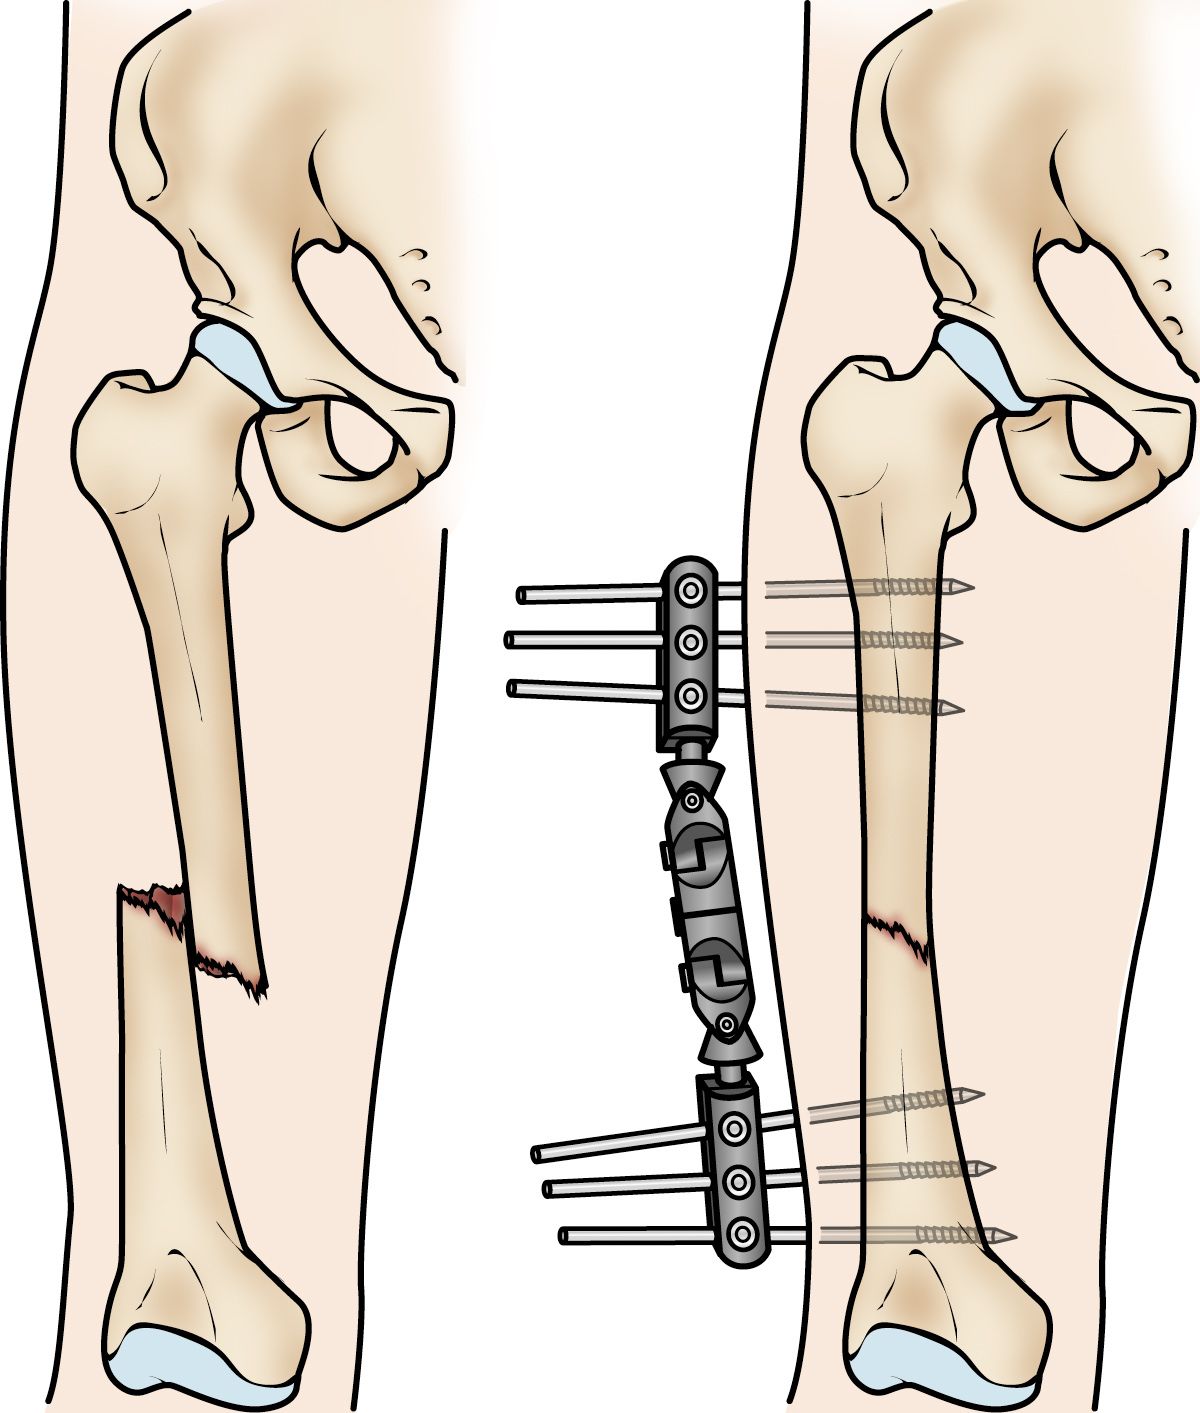

External fixation. In this type of operation, metal pins or screws are placed into the bone above and below the fracture site. The pins and screws are attached to a bar outside the skin. This device is a stabilizing frame that holds the bones in the proper position.

External fixation of a femoral shaft fracture

External fixation is often used to hold the bones together temporarily when the skin and muscles have been injured.

External fixation is usually a temporary treatment for femur fractures. Because they are easily applied, external fixators are often put on when a patient has multiple injuries and is not yet ready for a longer surgery to fix the fracture. An external fixator provides good, temporary stability until the patient is healthy enough for the final surgery. In some cases, an external fixator is left on until the femur is fully healed, but this is not common.